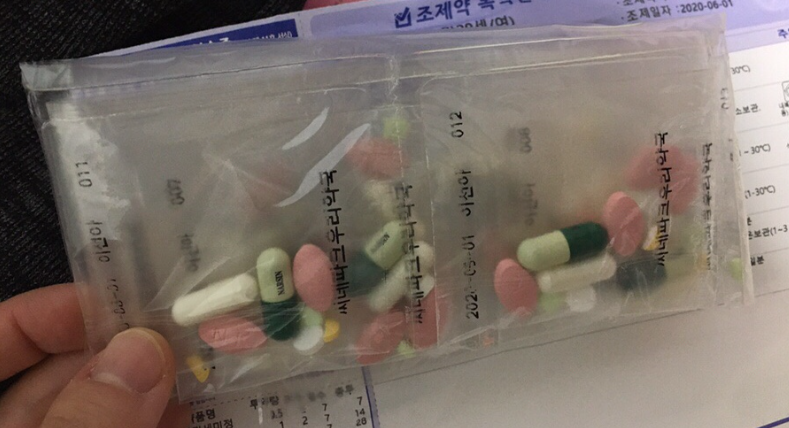

체질별 다이어트 처방약